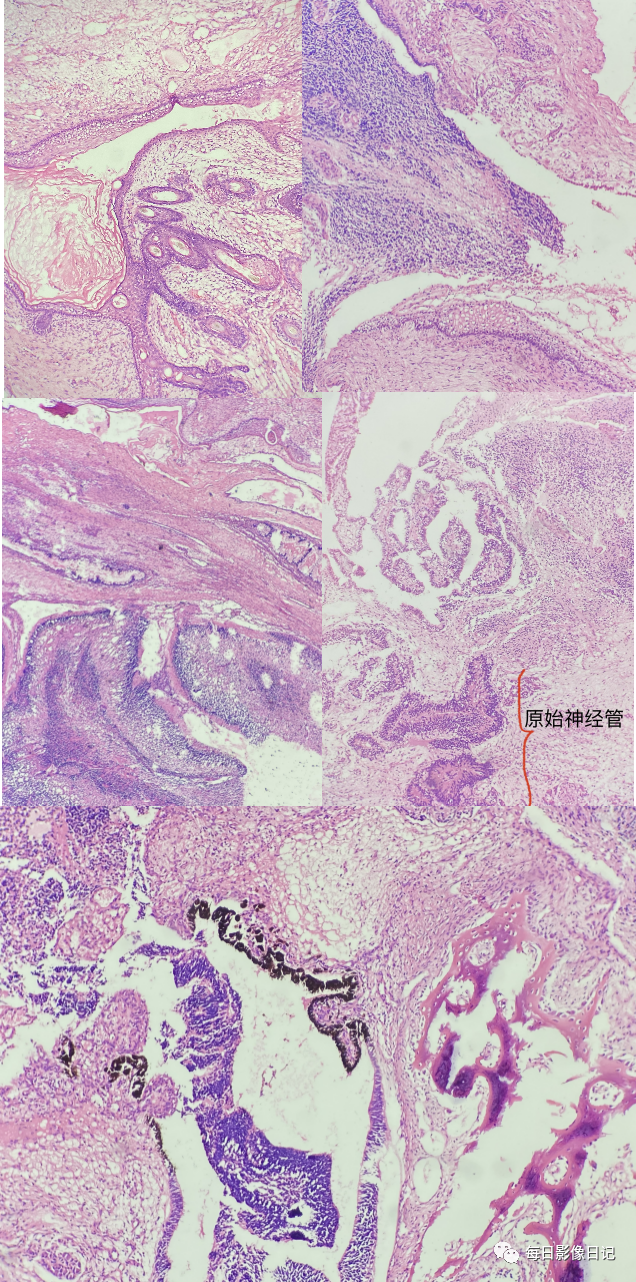

【病理】:

检查所见:输卵管1条,长8cm,最大经0.6cm,伞端可见,冰选:1.其下见结节样组织1个,大小,结节切面灰褐灰红,另见囊泡形成。肿块冰选2-6常规:输卵管7,肿块8-15大网膜:网膜组织一块,大小,其内未扪及确切结节。

检查结论:病理诊断:常规石蜡切片:“右附件”卵巢未成熟性畸胎瘤(分级:高级别)。输卵管未见肿瘤累及。(2#行免疫组化染色)“大网膜”网膜水肿、充血、淤血,未见肿瘤转移。第二次报告:IHC:AFP:(-)、SAll4(神经,+)、CEA(上皮,+)、CK(上皮,+)、EMA(上皮,+)、GFAP(神经,+)、S-100(神经,+)、(+)、P53灶(+)、Ki-16(+,30%),支持上述诊断。

概述:卵巢未成熟性畸胎瘤是一种较少见的卵巢恶性生殖细胞肿瘤,含2~3个胚层,由分化程度不同的未成熟胚胎组织构成,原始神经组织为主。主要发生于儿童及青年。容易转移,多沿腹膜扩散,转移部位盆腔及腹膜、大网膜、肝、肠系膜及浆膜、直肠窝、对侧卵巢等。